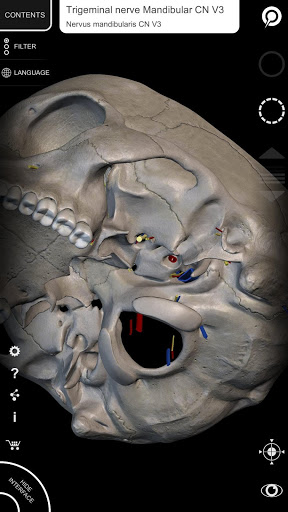

يتيح لك "Anatomy 3D Atlas" دراسة التشريح البشري بطريقة سهلة وتفاعلية.

من خلال واجهة بسيطة وبديهية، من الممكن ملاحظة كل بنية تشريحية من أي زاوية.

تتميز النماذج التشريحية ثلاثية الأبعاد بتفاصيل خاصة ودقة تصل إلى 4K.

يسهل التقسيم حسب المناطق والمناظر المحددة مسبقًا مراقبة ودراسة الأجزاء الفردية أو مجموعات الأنظمة والعلاقات بين الأعضاء المختلفة.

• الجهاز العصبي

• من خلال تحديد نموذج أو دبوس، يظهر المصطلح التشريحي ذي الصلة